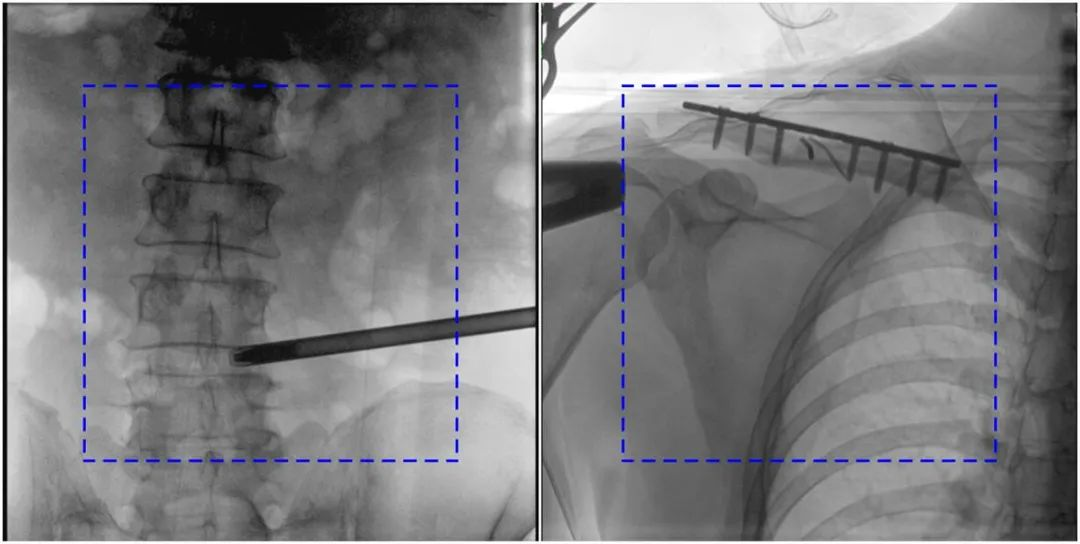

與傳統(tǒng)的21CM×21CM成像尺寸相比,普愛醫(yī)療大平板一體式C形臂具有30CM×30CM更大成像尺寸,能夠一次成像5.5節(jié)椎體,呈現(xiàn)更全面的影像信息,即便是手術(shù)經(jīng)驗不豐富的年輕醫(yī)生也能通過圖像迅速判斷椎體節(jié)段、定位手術(shù)部位,避免因為視野不足而造成的多次定位、反復曝光,提高效率的同時避免過量攝入輻射。

普愛醫(yī)療大平板一體式C形臂圖像與傳統(tǒng)圖像對比(藍色虛線內(nèi)為傳統(tǒng)21CM×21CM平板的成像區(qū)域)